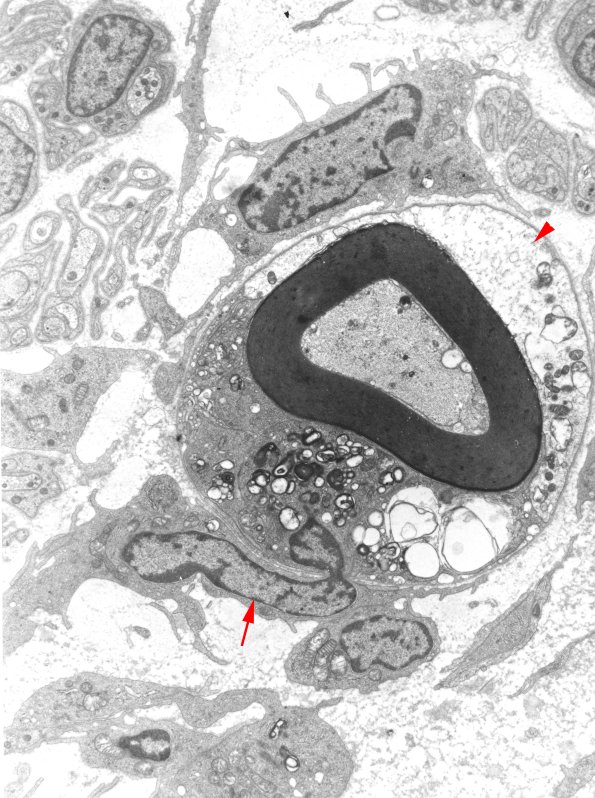

1D2A-C ---- 1D2A A macrophage (arrow) and a portion of its nucleus has insinuated itself through the Schwann cell cytoplasm and contains cytoplasmic myelin debris. The Schwann cell cytoplasm (arrowhead) in these cases is often very pale and watery. I am not sure if it will subsequently degenerate to be replaced by others or survive. (electron micrograph)